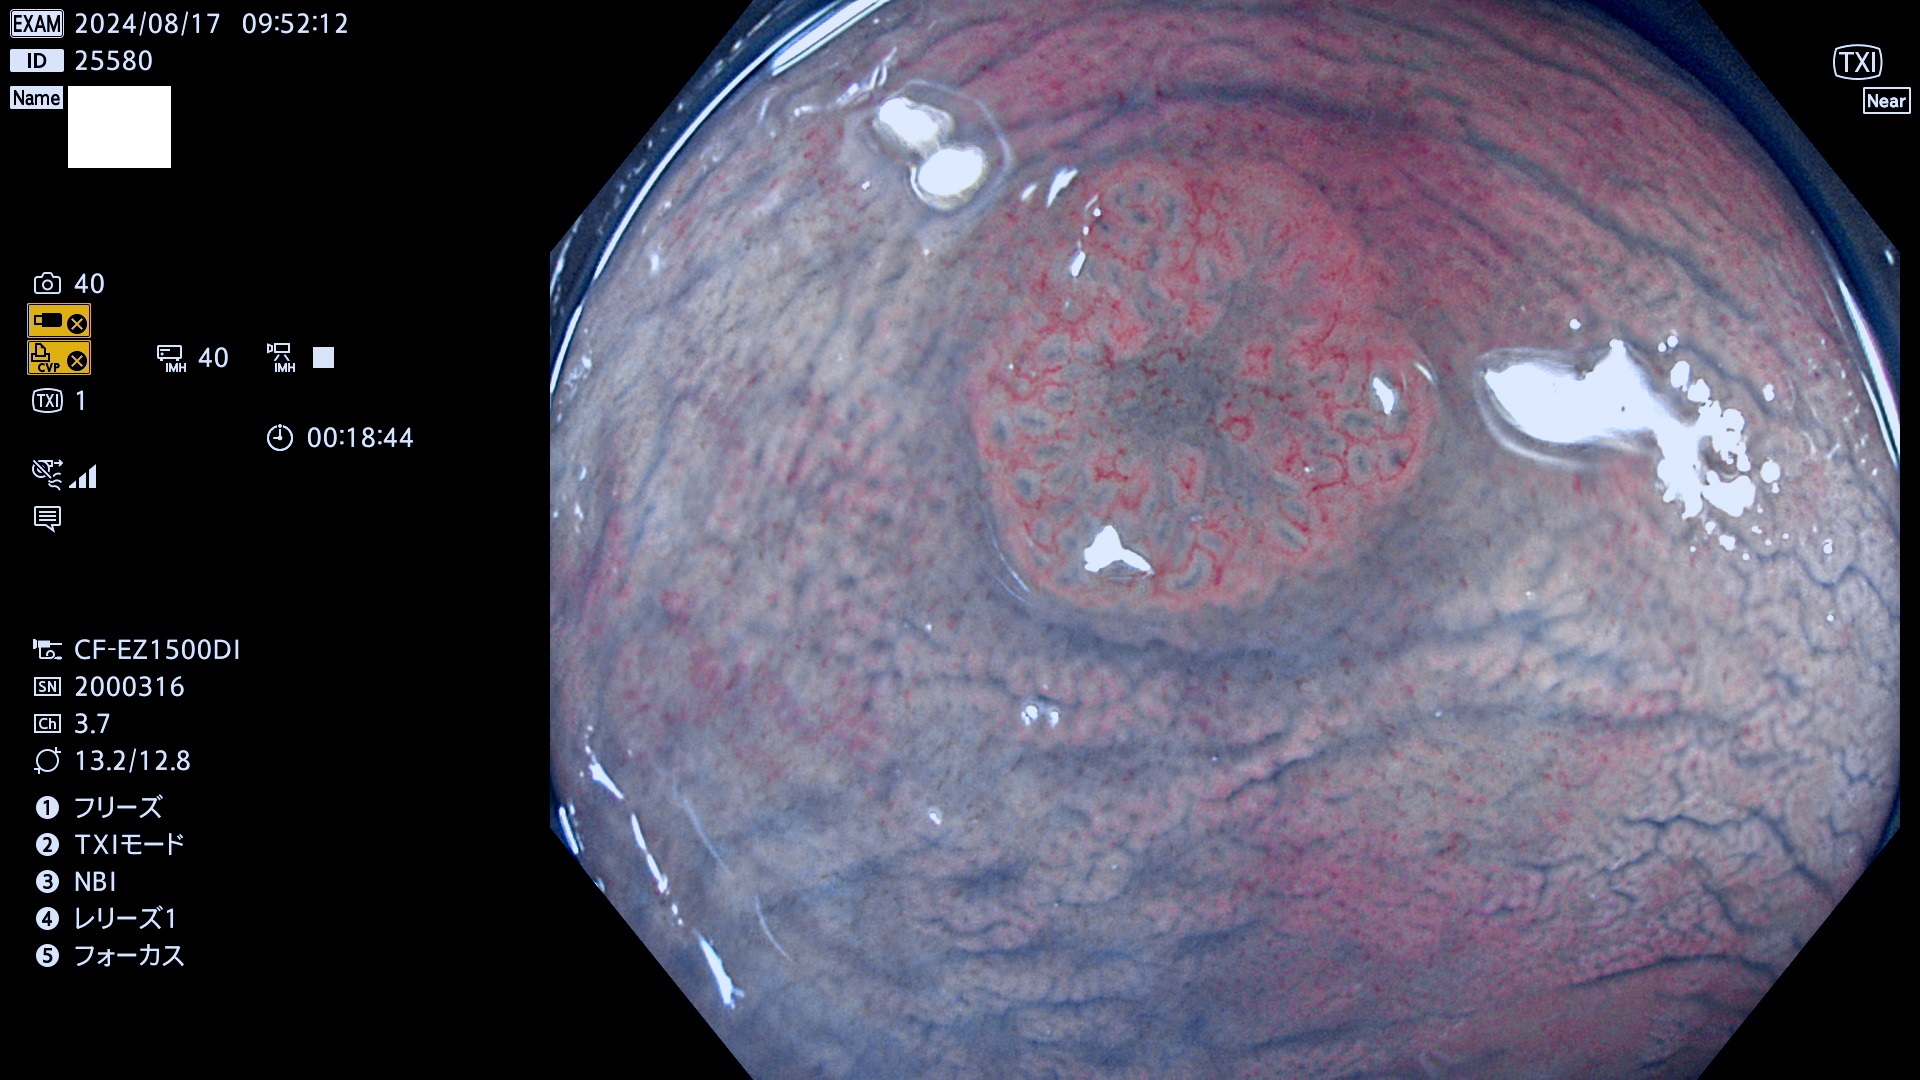

今週のUb、Uc型腺腫

完全に平坦な物をUb、陥凹している物をUcと呼びます。最も発見が難しく危険な病変です。

抽出の対象期間 2024年8月15日〜8月18の4日間(33件の検査)7件 (7/33=21%)